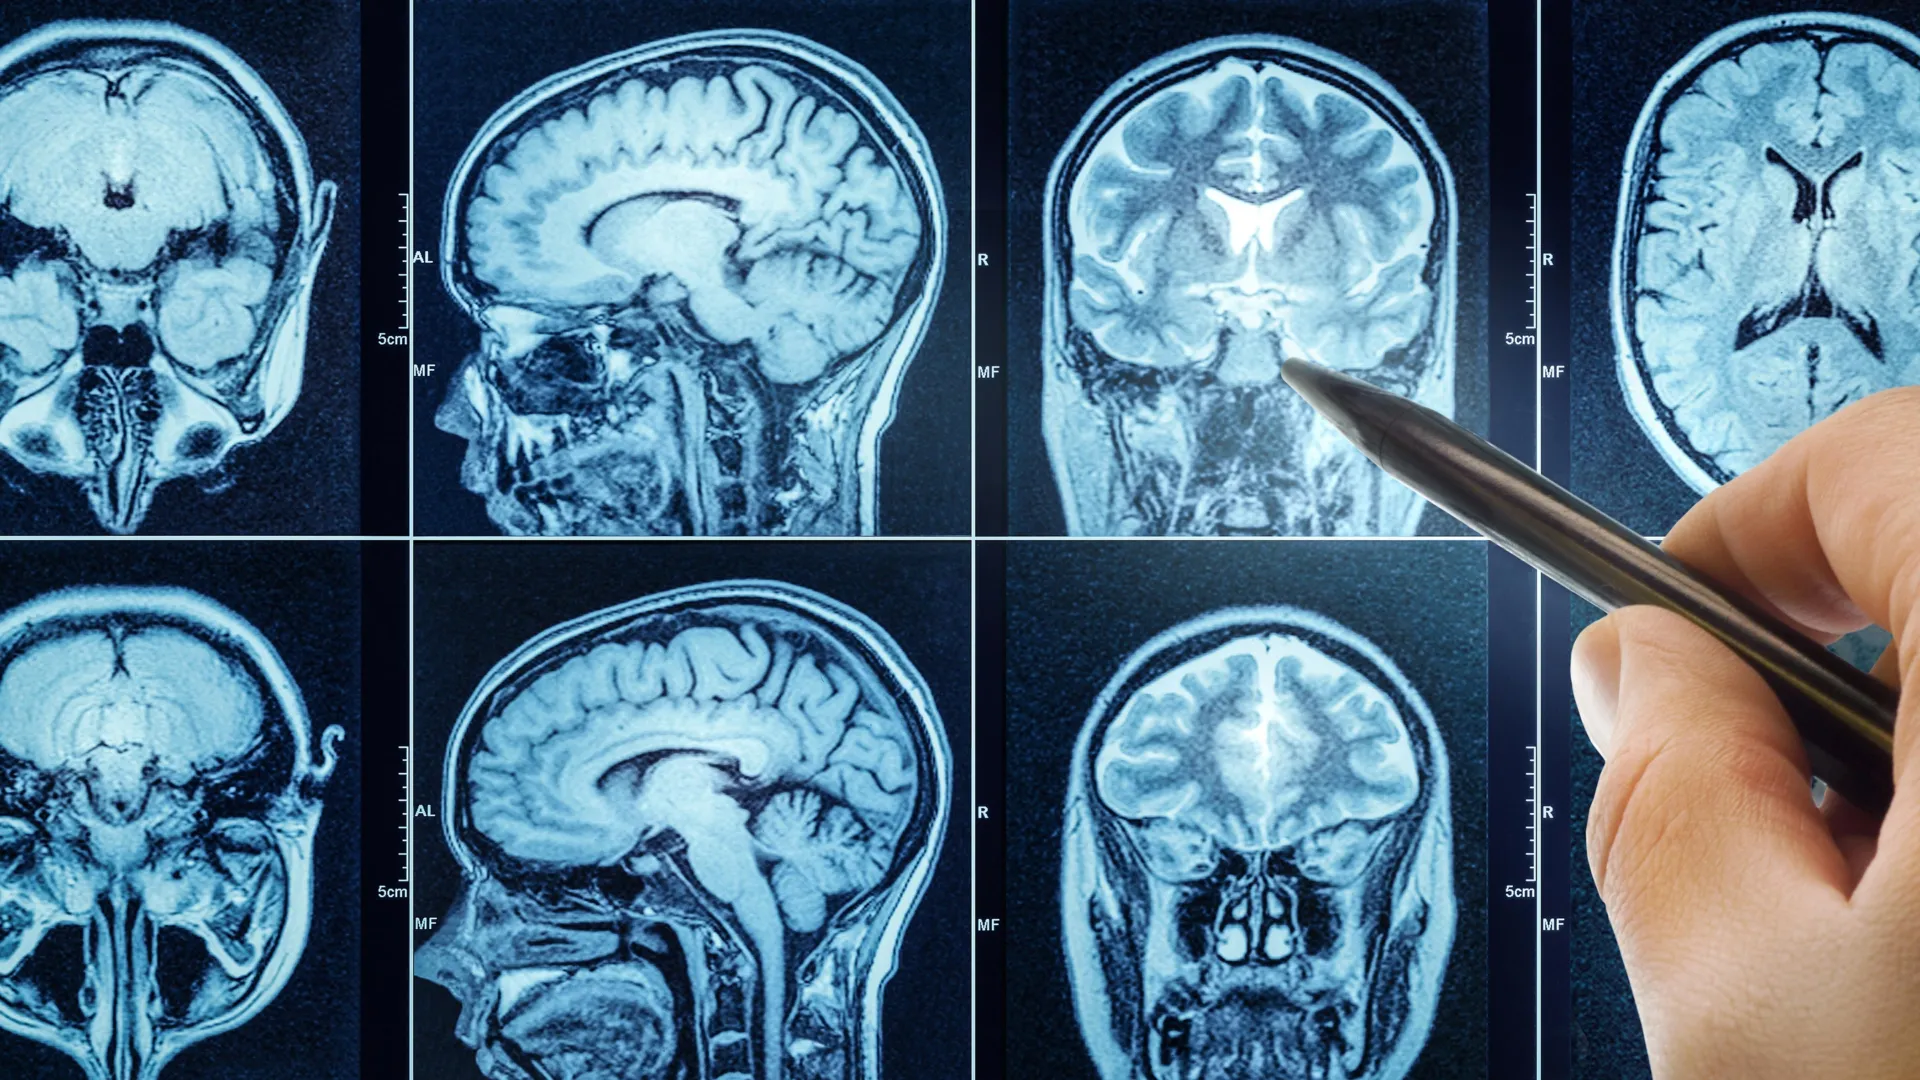

The study includes 27,500 middle-aged and older people from the UK Biobank who underwent magnetic resonance imaging (MRI) of the brain. Using machine learning, the researchers estimated the biological age of the brain based on over a thousand brain MRI phenotypes.